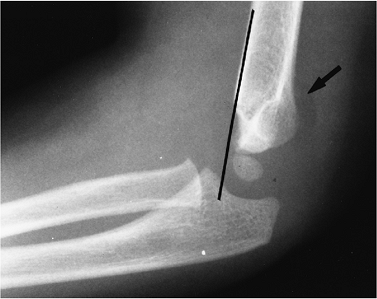

![]() |

FIGURE 8-2 Supracondylar fracture line is not clearly seen, but the capitulum lies posterior to the anterior humeral line (black line),

indicating a fracture. The anterior humeral line should intersect the midcapitellum. There is also a positive posterior fat pad sign (arrow). |